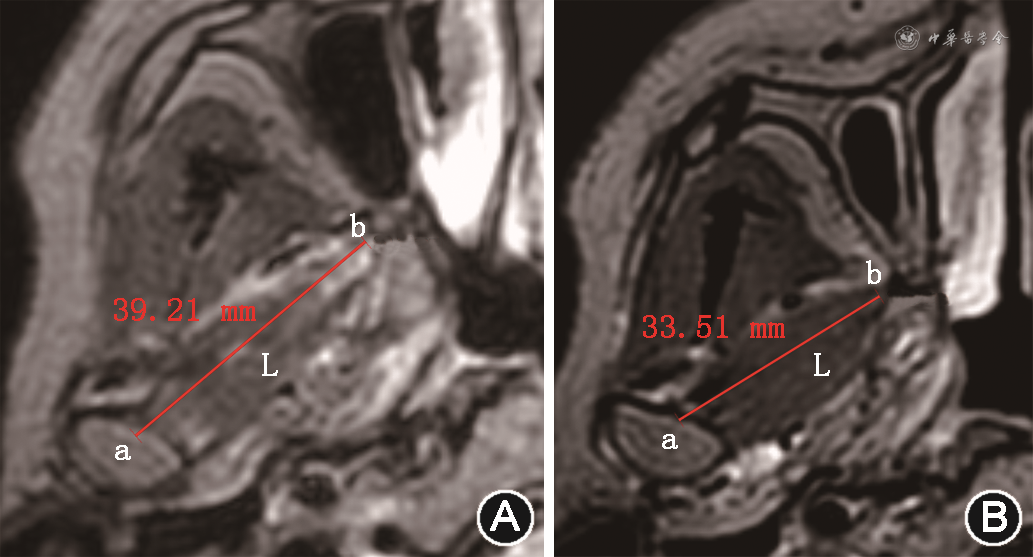

翼外肌收缩程度与关节盘移位相关[5,16],尤其是上头。翼外肌痉挛可致关节盘移位[5],关节盘可复性移位时翼外肌上头功能代偿致活动过度[1],当病情进展致不可复性移位时,翼外肌功能失代偿致肌肉萎缩,活动减低[5,16]。三维T2WI-FS是采用三维薄层容积采集,可通过多平面重建技术重建翼外肌,在斜轴位图像获取翼外肌上头最大截面,测量张口位及闭口位翼外肌上头最大长度(图5),两者差值即为翼外肌上头收缩长度,反映其运动功能[16]。关节盘不可复性移位翼外肌收缩度显著低于可复性移位,可作为评估TMD严重程度的一个影像学指标[16]。

注:a点为髁突中点;b点为翼外肌上头;线段L为翼外肌上头长轴长度